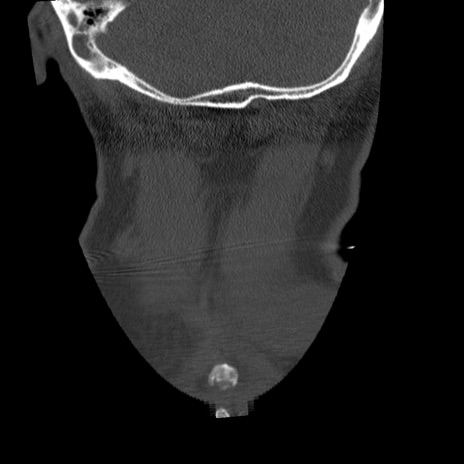

症例50 頚椎CT(冠状断像)

頚椎CT